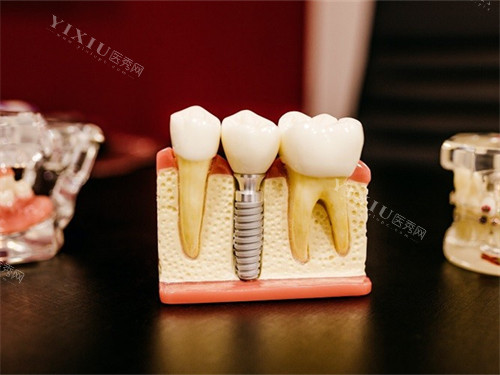

手术风险:

种植牙手术可能引发周围神经损伤、上颌窦穿孔等术中并发症,术后存在感染、出血等风险。

种植牙需长期维护,若保养不当,可能导致牙周疾病、口腔发炎等问题。

部分患者因忽视口腔卫生,导致种植体周围组织退化,影响种植牙的稳固程度。